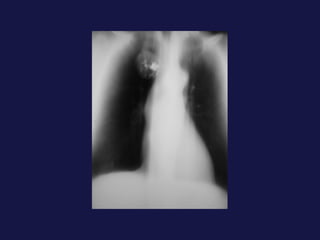

Tumor central. 60-75% próximos a los hilios. Epidermoides y células pequeñas. Agrandamiento asimétrico del hilio o masa de bordes espiculados. Atelectasia lobular, segmentaria o de todo el pulmón. Sobreinfección del parénquima distal y neumonía postobstructiva, a menudo abscesificada.

Extensión local y a distancia. Afectación  hiliar Invasión de la pared torácica (Pancoast). Afectación  pleural ( 8-15%). Afectación mediastínica. Linfangitis carcinomatosa. Metástasis extratorácicas.

Tumor central. 60-75%próximos a los hilios. Epidermoides y células pequeñas. Agrandamiento asimétrico del hilio o masa de bordes espiculados. Atelectasia lobular, segmentaria o de todo el pulmón. Sobreinfección del parénquima distal y neumonía postobstructiva, a menudo abscesificada.

Extensión local ya distancia. Afectación hiliar Invasión de la pared torácica (Pancoast). Afectación pleural ( 8-15%). Afectación mediastínica. Linfangitis carcinomatosa. Metástasis extratorácicas.